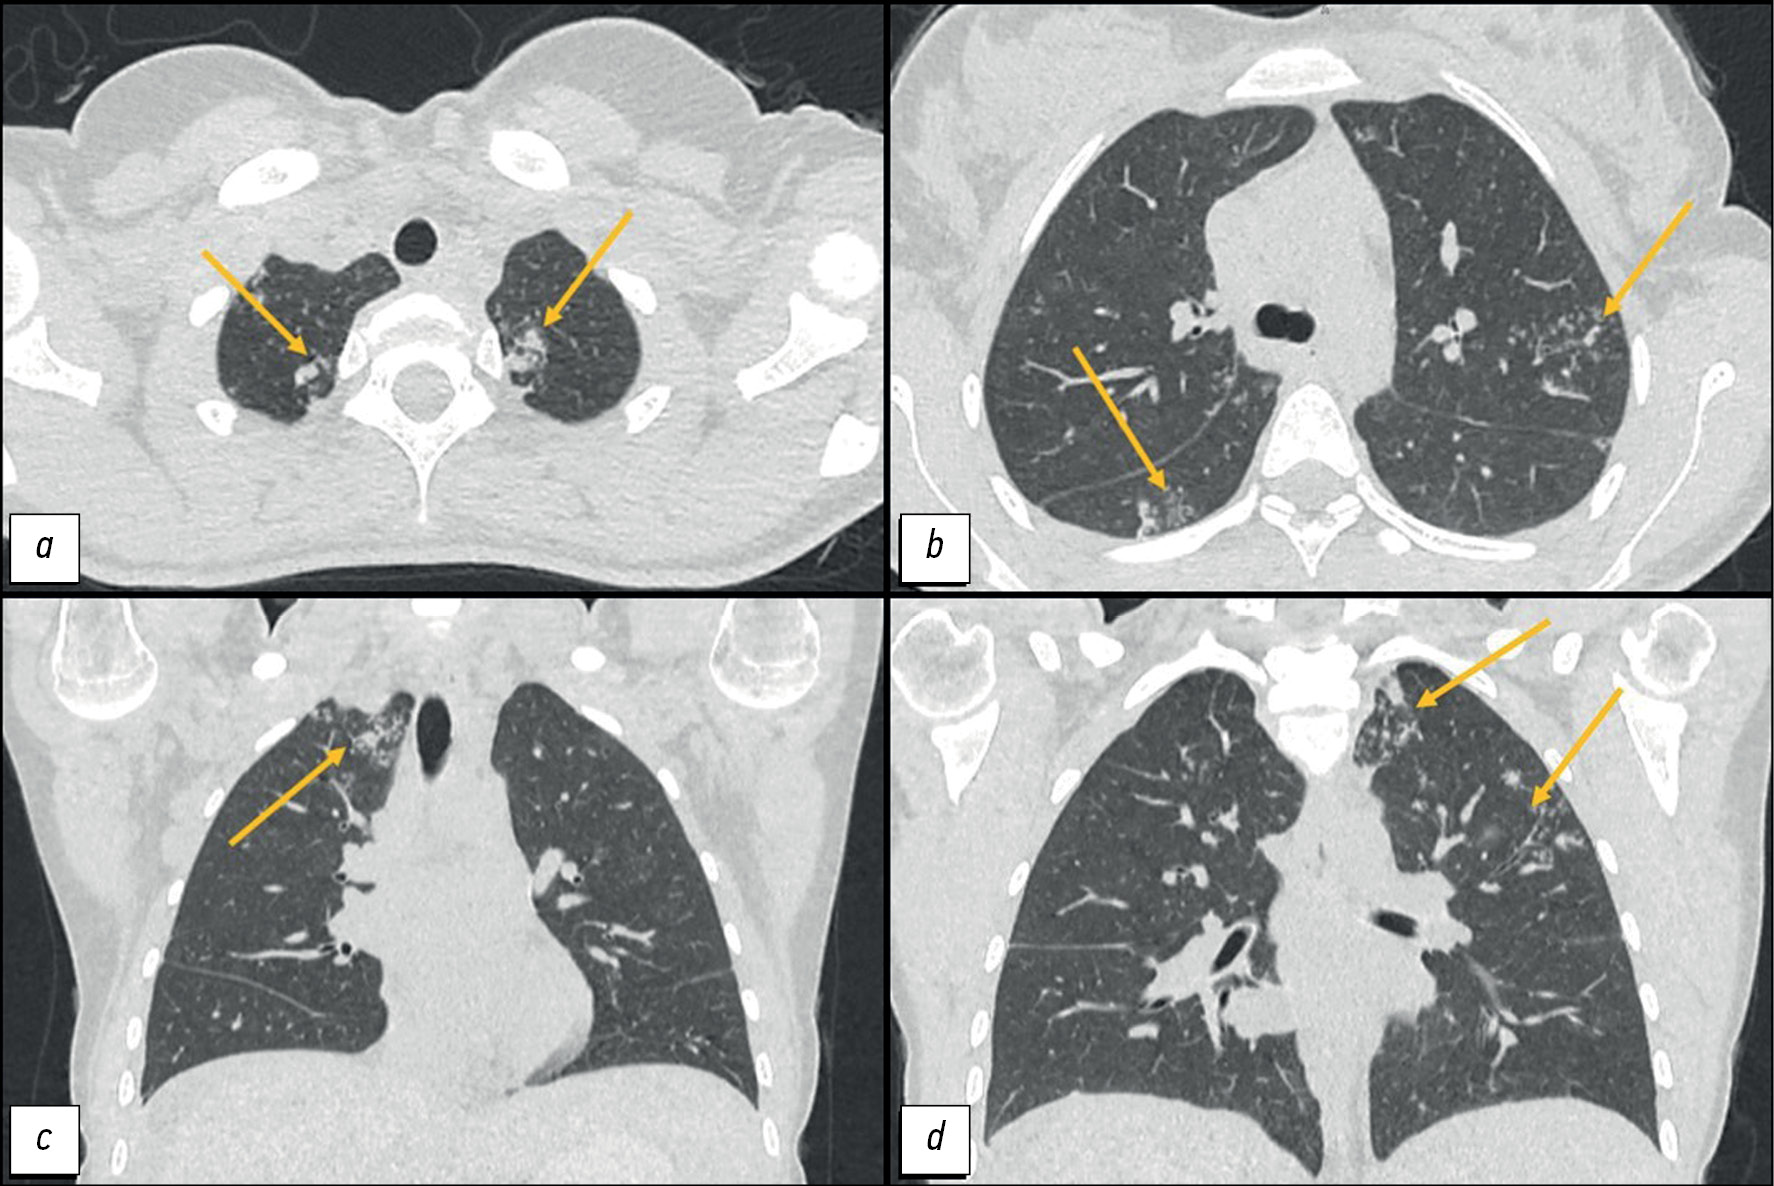

CT of the lungs showed the following:

- In segments I, II, and VI: “tree-and-bud” structures and peribronchial lesions up to 8 mm in size with a tendency to merge.

- In the apex of the left lung: an irregularly shaped subpleural consolidation zone of 15 × 11 mm,

- Mediastinal lymphadenopathy of up to 12 mm (Figure 1).

Fig. 1. Computed tomography of the chest organs: a, d - axial plane; b, c — coronal plane. Arrows indicate peribronchial foci and zones of consolidation in the apices of the lungs.